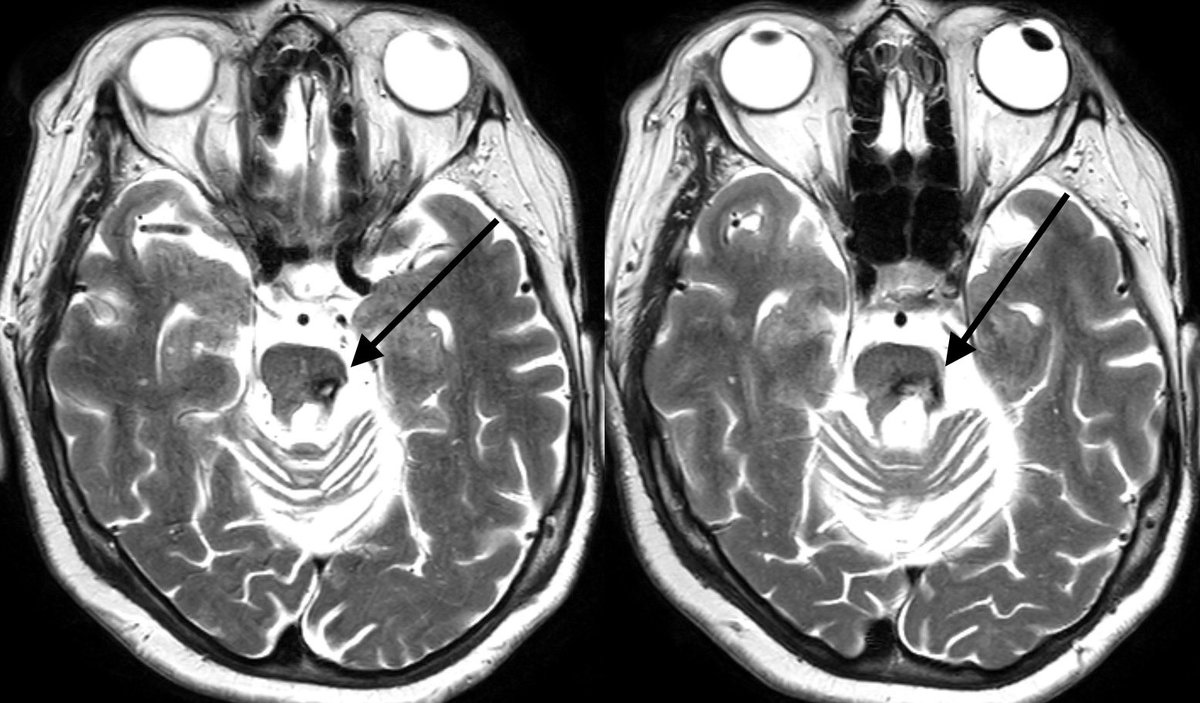

Lesions that disrupt the triangle of Guillain and Mollaret (neural pathway connecting the red nucleus, inferior olivary nucleus, and contralateral dentate nucleus) can result in swollen inferior olivary nuclei

Imaging: T2/FLAIR bright and swollen inferior olivary nuclei w/o enhancement